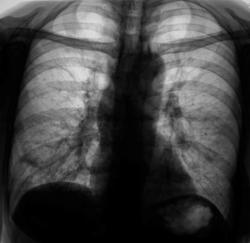

После проведения противовоспалительной терапии проведен "контроль".

Ваше мнение уважаемые коллеги?

А млжет быть эти крупные очаги - метастазы?

очень может быть...

По всей видимости, придется направить на консультацию к онкологам.